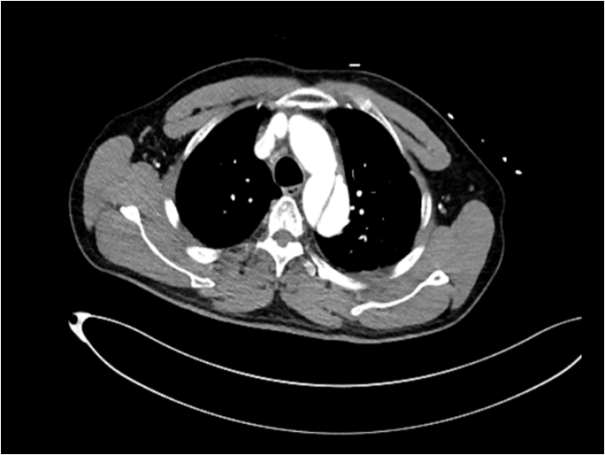

48岁男性,突发上腹剧烈疼痛伴有大汗淋漓,既往多年高血压病史。

五、主动脉夹层诊断

时间就是生命。医生会结合症状,快速进行以下检查:医院会根据CT血管成像(CTA)进行诊断。如确诊为主动脉夹层,则会进行紧急处理,立即镇痛、控制血压和心率(如静脉注射β受体阻滞剂)。